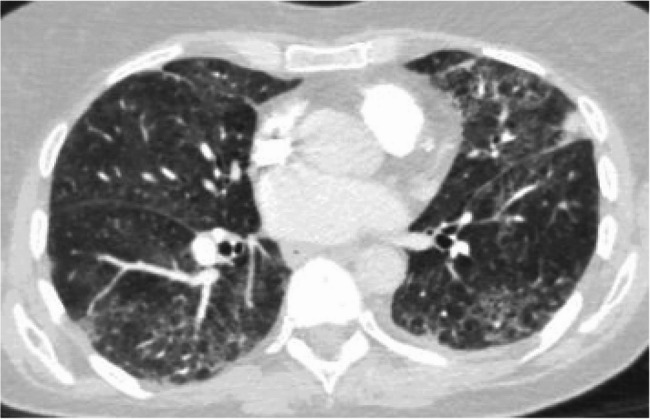

Case report: We discuss a 73-year-old woman with newly diagnosed DLBCL who underwent chemotherapy and immunotherapy with rituximab, cyclophosphamide, doxorubicin hydrochloride, vincristine sulphate, and prednisone (R-CHOP). Following her initial rituximab infusion, she developed shortness of breath, chills, rigors, flushing, and agitation. The rituximab infusion was paused, and hypersensitivity reaction medications were given per protocol. The infusion was resumed at a slower rate. Two weeks after initial infusion, she was hospitalized for shortness of breath and hypoxemia to 88% on pulse oximeter requiring 2 L of nasal cannula oxygen. Chest imaging showed new diffuse ground glass opacities (GGOs) on top of apical scarring, upper lobe emphysema, and few calcified granulomas. Patient underwent bronchoscopy for bronchoalveolar lavage (BAL) which was negative for infections and malignancy. Given the temporal relationship, chemotherapy induced lung injury was high on the differential, with rituximab being the possible offending agent. She was started on prednisone 60 milligram for 5 days with a follow up chest imaging showing resolution of the acute GGO. Her O2 requirements decreased from 3 L to 1 L and she was sent home with oxygen. Given the curative intent of R-CHOP, after shared decision making with the patient and her medical team, a treatment plan with a longer course of high and low prednisone was incorporated as part of her chemotherapy session. She was able to successfully finish her treatment with no additional episode, at which point she was able to be successfully tapered off her prednisone.